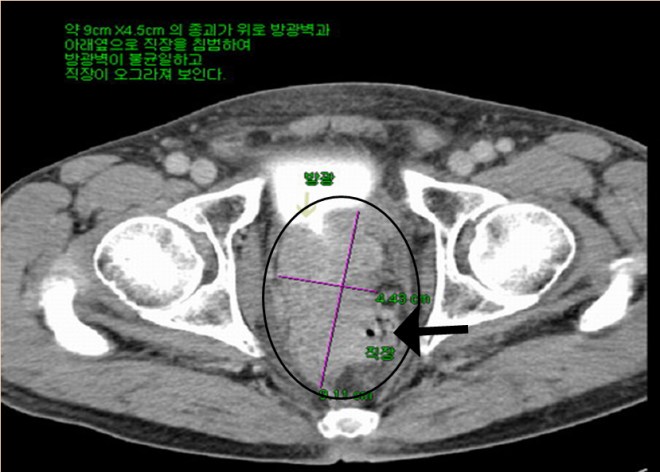

전립선암이 열어 보니 방광 대장을 다 침범하여서 거의 9cm 이상의 종양이 퍼져 있었고, 주변 ischial lymph node(골반 주위의 림프절)의 다발성전이가 있었던 분이다. 이후 본원에 와서 양방에서는 사용치 않는 양성 전립선비대를 억제하는 프로스카와 본원의 한방요법을 결합하여 전립선암이 거의 없어진 상태로  3년 이상을 정상생활을 하였고 그 후 술 담배를 다시 하기 시작하고 일년만에 다발성 폐전이가 되어서 폐렴합병증으로 사망한 사례이다. 자료를  2000 년도의 자료라 찾기가 어려워서 나중에 더 보충 자료를 넣어 보려고 하지만 본고에서는  2007 년도 본인이 삼성의료원의 산부인과 배덕수 과장 소개로 한의학의 암치료에 대한 강의를 초청받아서 갔을 때 자료를 가지고 이 환자의 사례를 설명해 보겠다.

1-2.JPG

나이는 74세로 당시 뼈전이와 골반벽전이 대장방광전이가 있어서 열었다 바로 닫아버리고  2달선고를 받고 나서 한방을 찾았다. 위에서 보듯이 경추에 전이가 있었고, 아래 사진과 같이 약 9cm 정도의 종양이 방광벽을 침범하여서 방광이 일그러져 보이고(하얀 소변이 찬 부분 아래쪽면) 대장도 밀려서 화살표에서 보는 작은 점이 남아 있는 대장의 크기로 대변을 거의 못 보다시피 가늘게 나왔다.

1-5.jpg

위의 CT에서 보듯이 왼쪽 사진에 흰 화살표와 검은 화살표로 경계 지어지는 부분은 왼쪽 골반뼈에 접한 림프절인데 거의 10cm 이상을 육박하고 우측 사진에서는 위쪽은 방광벽, 아래로는 대장을 침범한 사진을 볼 수 있다. 워낙이 복부에 퍼져 있어서 바로 보고 닫았다고 한다.